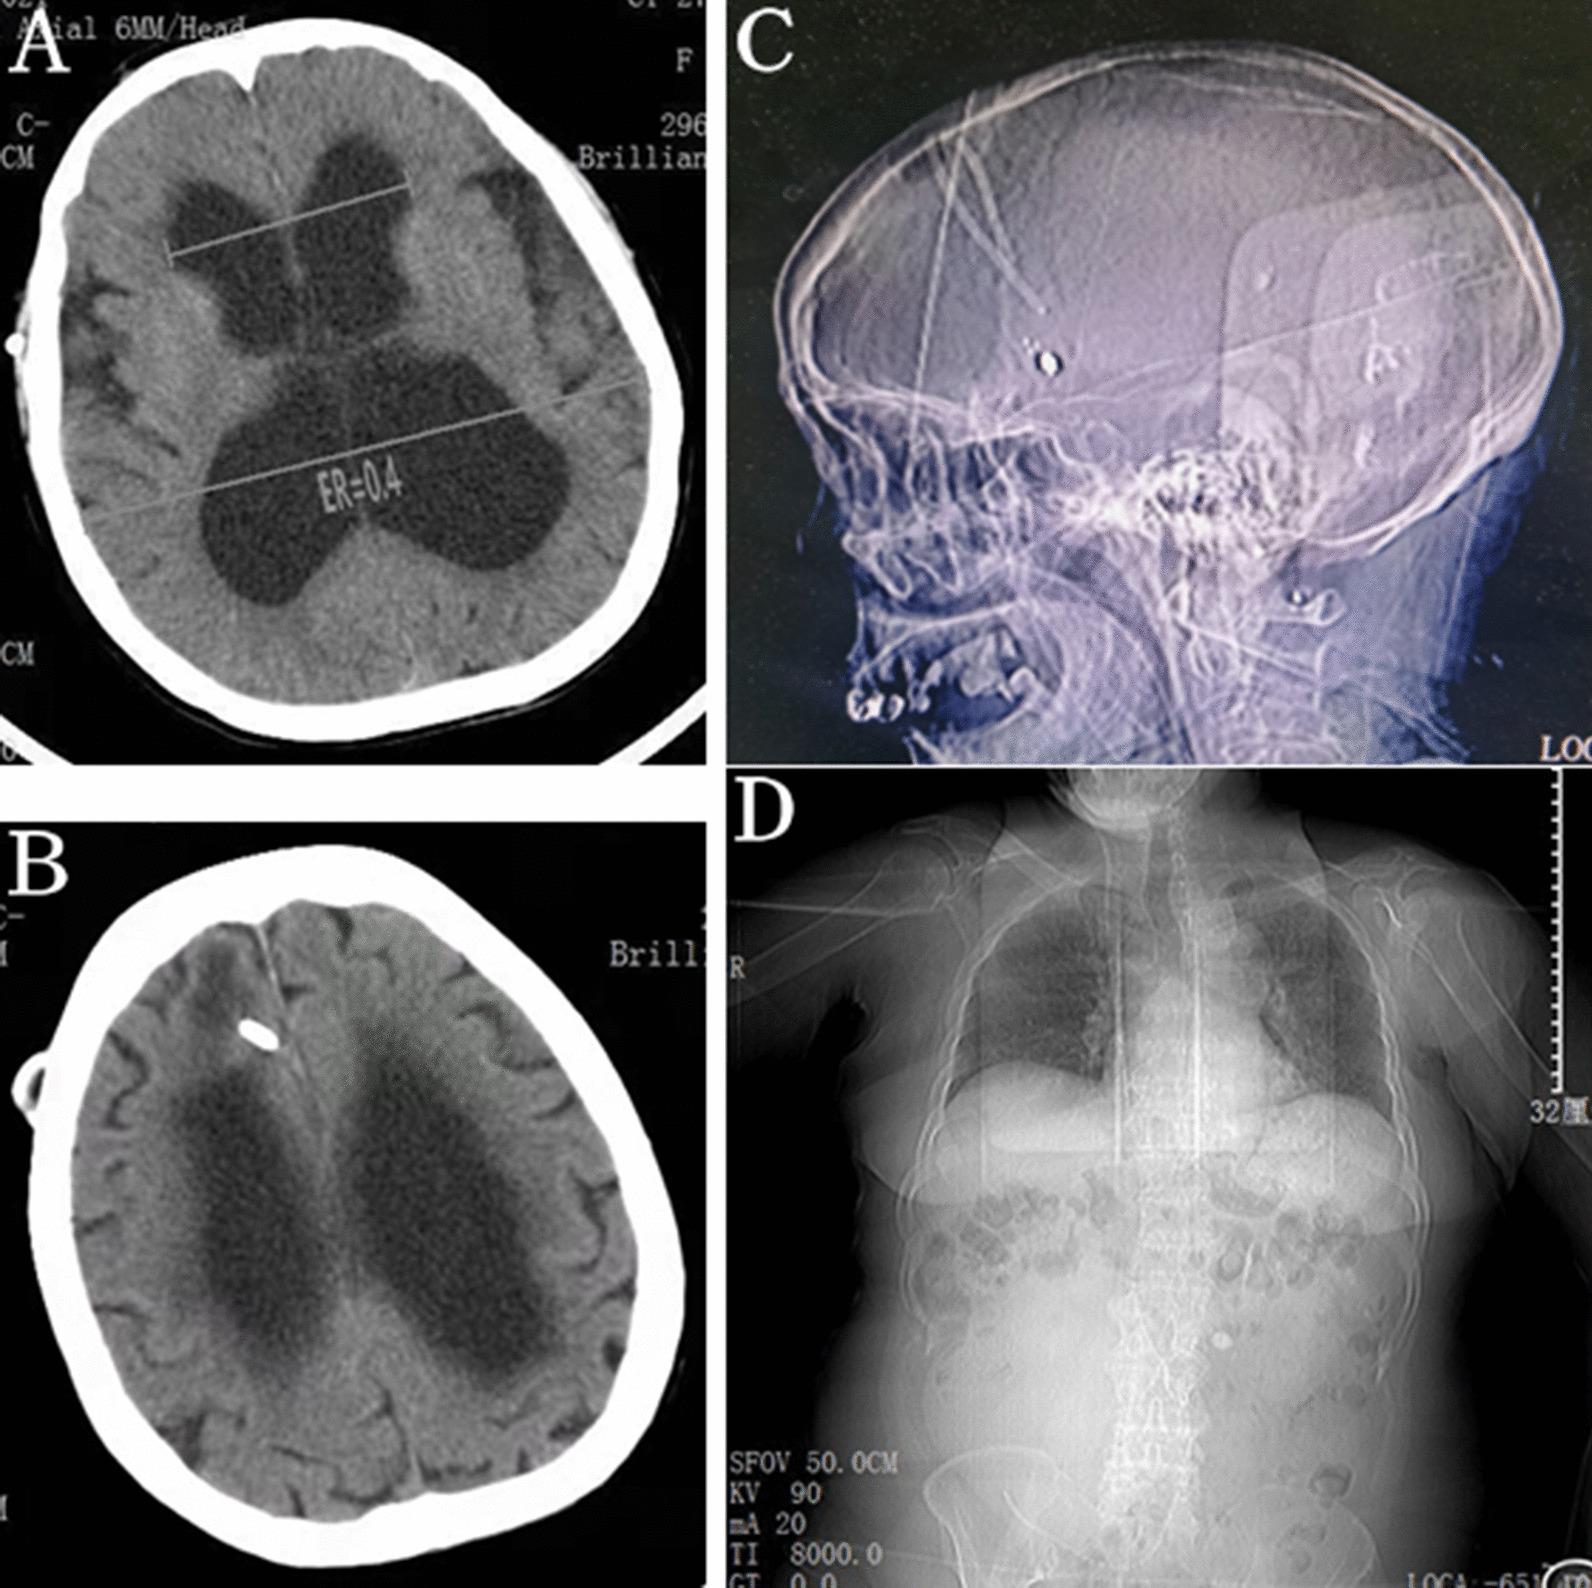

Unenhanced abdominal computed tomography (CT) scan indicated a large cystic collection of homogenous iso-density fluid in the right lower abdominal region with clear margins (Fig. 1a). The distal segment of the peritoneal shunt catheter was located within the cystic mass (Fig. 1b). The cystic mass, independent from the abdominal viscera, was nonloculated and 25–30 Hounsfield units in attenuation. There was no colonic obstruction. Dilation of the ventricular system was found on the cerebral CT imaging and the Evans Ratio (ER) value was 0.4 (Fig. 2a). Although the ventricular system was enlarged, interstitial cerebral edema and hemorrhage in brain or along the catheter were not found (Fig. 2b). Moreover, the trajectory of the shunt on the skull and abdomen–thorax X ray did not show the catheter breakage, disconnection or migration (Fig. 2c, d). Abdominal CSF pseudocyst was highly suspected as a preoperative diagnosis.

Fig. 2.

a Cerebral CT showed an enlarged ventricular system and its Evans Ratio was 0.4. b There being no interstitial cerebral edema and hemorrhage in brain or along the catheter. c, d The trajectory of the shunt on the skull and abdomen–thorax X ray did not show the catheter breakage, disconnection or migration